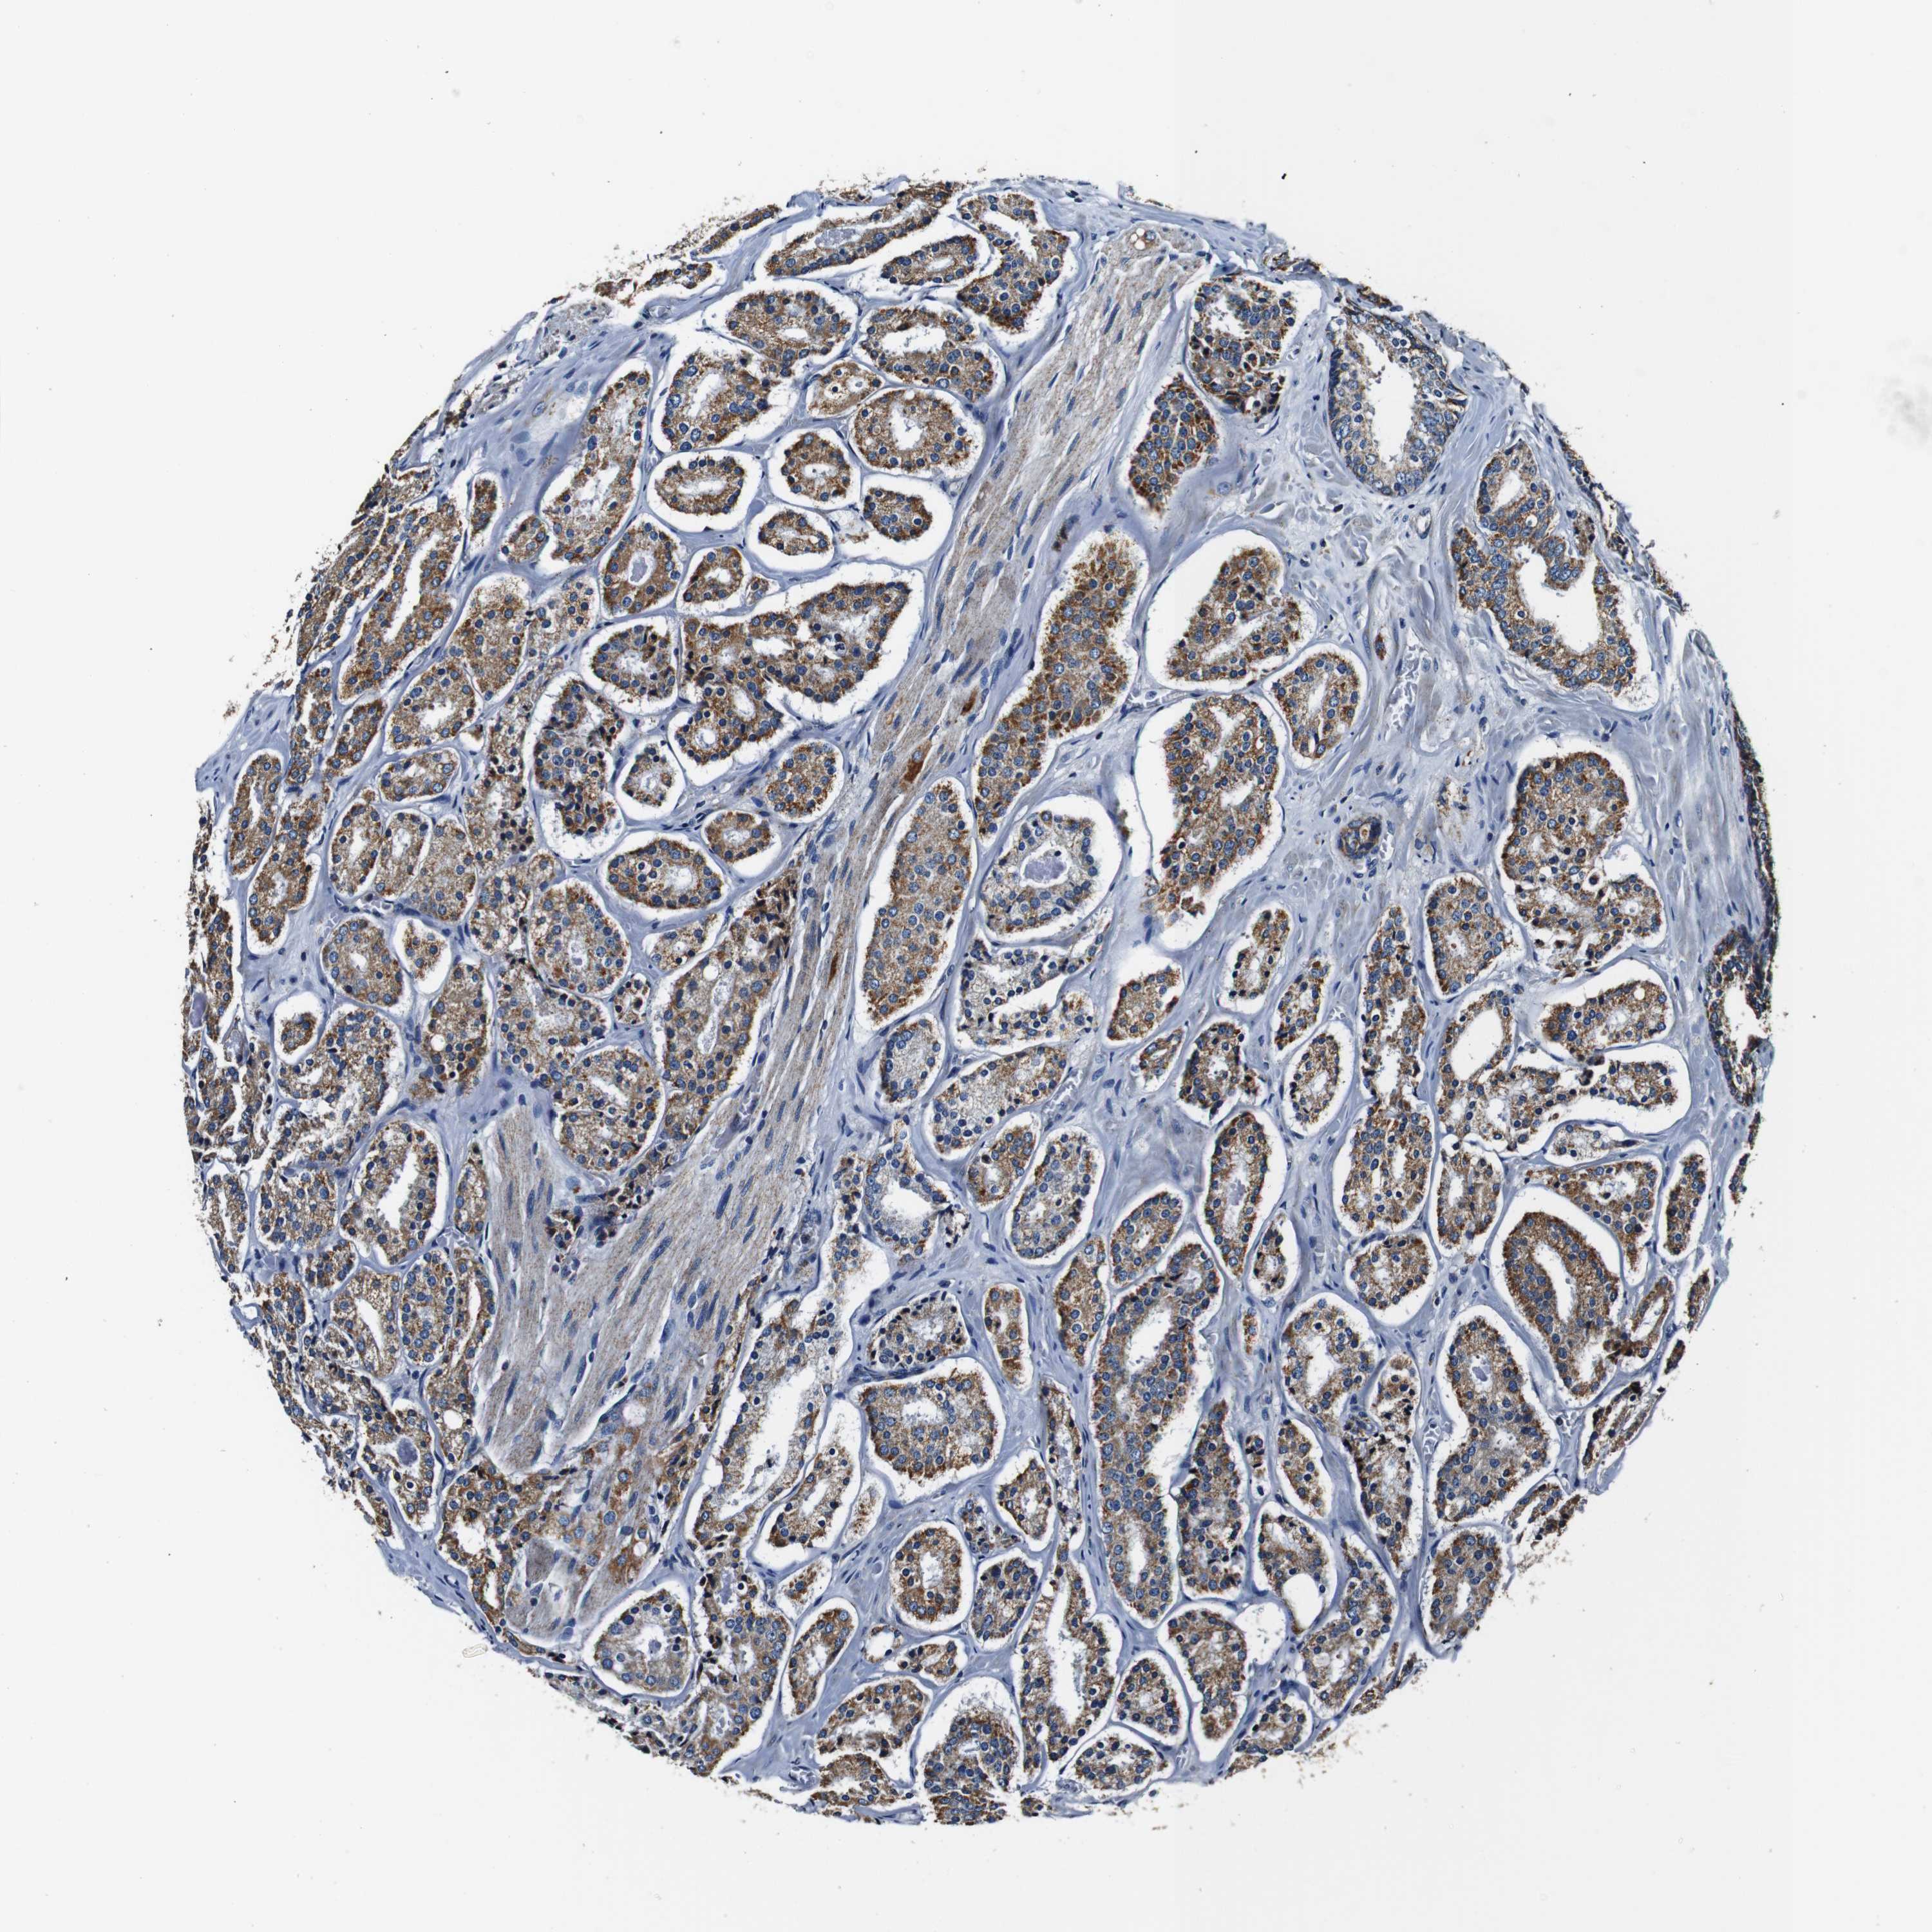

PROSTATE CANCER - Protein expressioni

A mouse-over function shows sample information and annotation data. Click on an image to view it in a full screen mode. Samples can be filtered based on level of antibody staining by selecting one or several of the following categories: high, medium, low and not detected. The assay and annotation is described here.

Note that samples used for immunohistochemistry by the Human Protein Atlas do not correspond to samples in the TCGA dataset.

Antibody stainingi

Antibody staining in the annotated cell types in the current human tissue is reported as not detected, low, medium, or high, based on conventional immunohistochemistry profiling in selected tissues. This score is based on the combination of the staining intensity and fraction of stained cells.

Each image is clickable and will lead to virtual microscopy that enables deeper exploration of all samples and also displays staining intensity scores, fraction scores and subcellular localization as well as patient and tissue information for each sample.

Antibody HPA007043

Antibody HPA007044

Antibody CAB010052

Staining

High

Medium

Low

Not detected

Intensity

Strong

Moderate

Weak

Negative

Quantity

>75%

75%-25%

<25%

None

Location

Nuclear

Cytoplasmic/membranous

Cytoplasmic/membranous,nuclear

Adenocarcinoma, Low grade

Adenocarcinoma, High grade